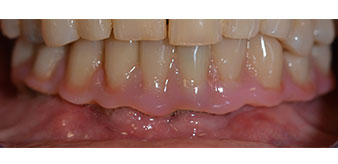

Die 64-jährige Patientin wurde mit einer Unterkiefer-Restbezahnung 38, 33 und 43 und einer klammerbefestigten Interimsprothese im Unterkiefer vorstellig (Abb. 1 und 2).

Unterkiefer-Restbezahnung

Abb. 1

Abb. 2

Die notwendige parodontologische Behandlung und Extraktion im Oberkiefer sollte zu einem späteren Zeitpunkt erfolgen, da die Patientin Lehrerin ist und zu dem Zeitpunkt mit Abiturprüfungen beschäftigt war. Sie konnte weder essen noch adäquat sprechen, da die Interimsprothese sehr häufig und bei der kleinsten Belastung brach.